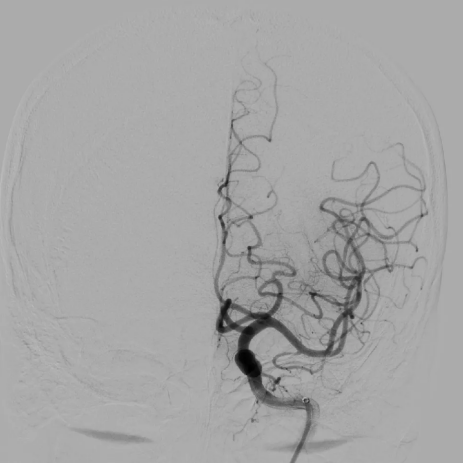

(患者术后血管血流恢复)

术后刘先生的语言功能立即恢复。经专业术后护理,第三天他的语言、肢体活动完全正常,各项指标稳定。目前,刘先生已康复出院,回归正常生活。